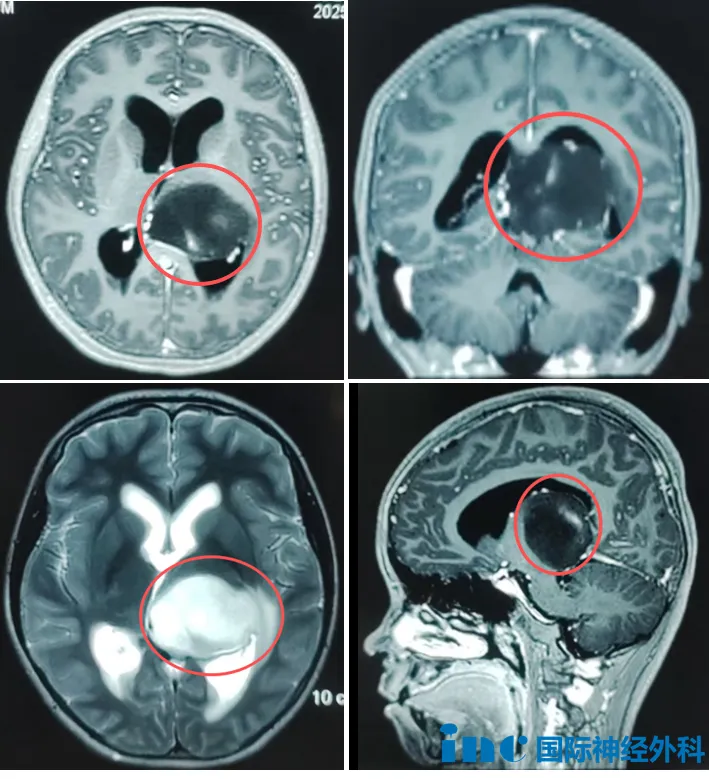

12岁的女孩诺诺,突发头晕,呕吐、食欲差,检查发现左侧丘脑占位,大小约37mm*45mm*40mm,三脑室受压,两侧脑室增宽。对于诺诺父母而言,孩子确诊脑瘤犹如晴天霹雳,恨不能立刻手术“一刀了断”。然而,若巨大肿瘤位于大脑深部,又该如何抉择?